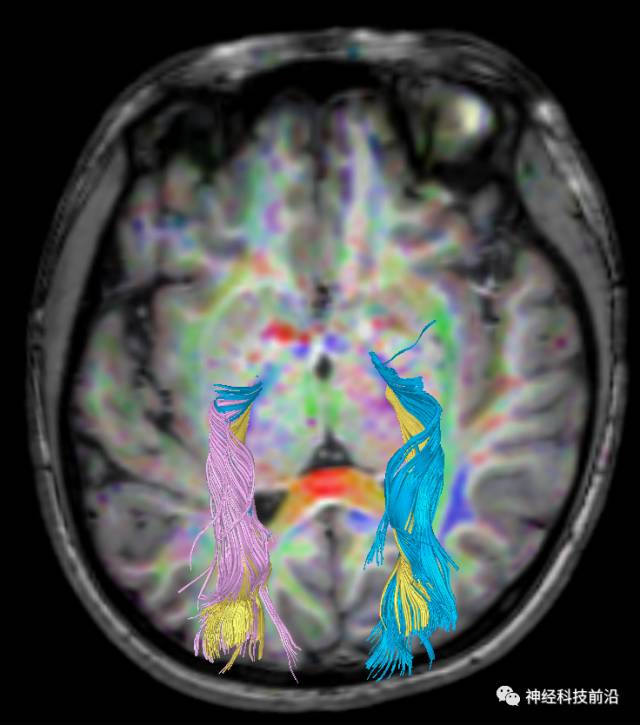

皮质脑桥束与脑干高信号(黄色)纤维束

皮质脊髓束与皮质脑桥束的关系毗邻

脑干内高信号为一近环形纤维束,其作用尚待研究。

上述纤维束与小脑中脚的位置毗邻